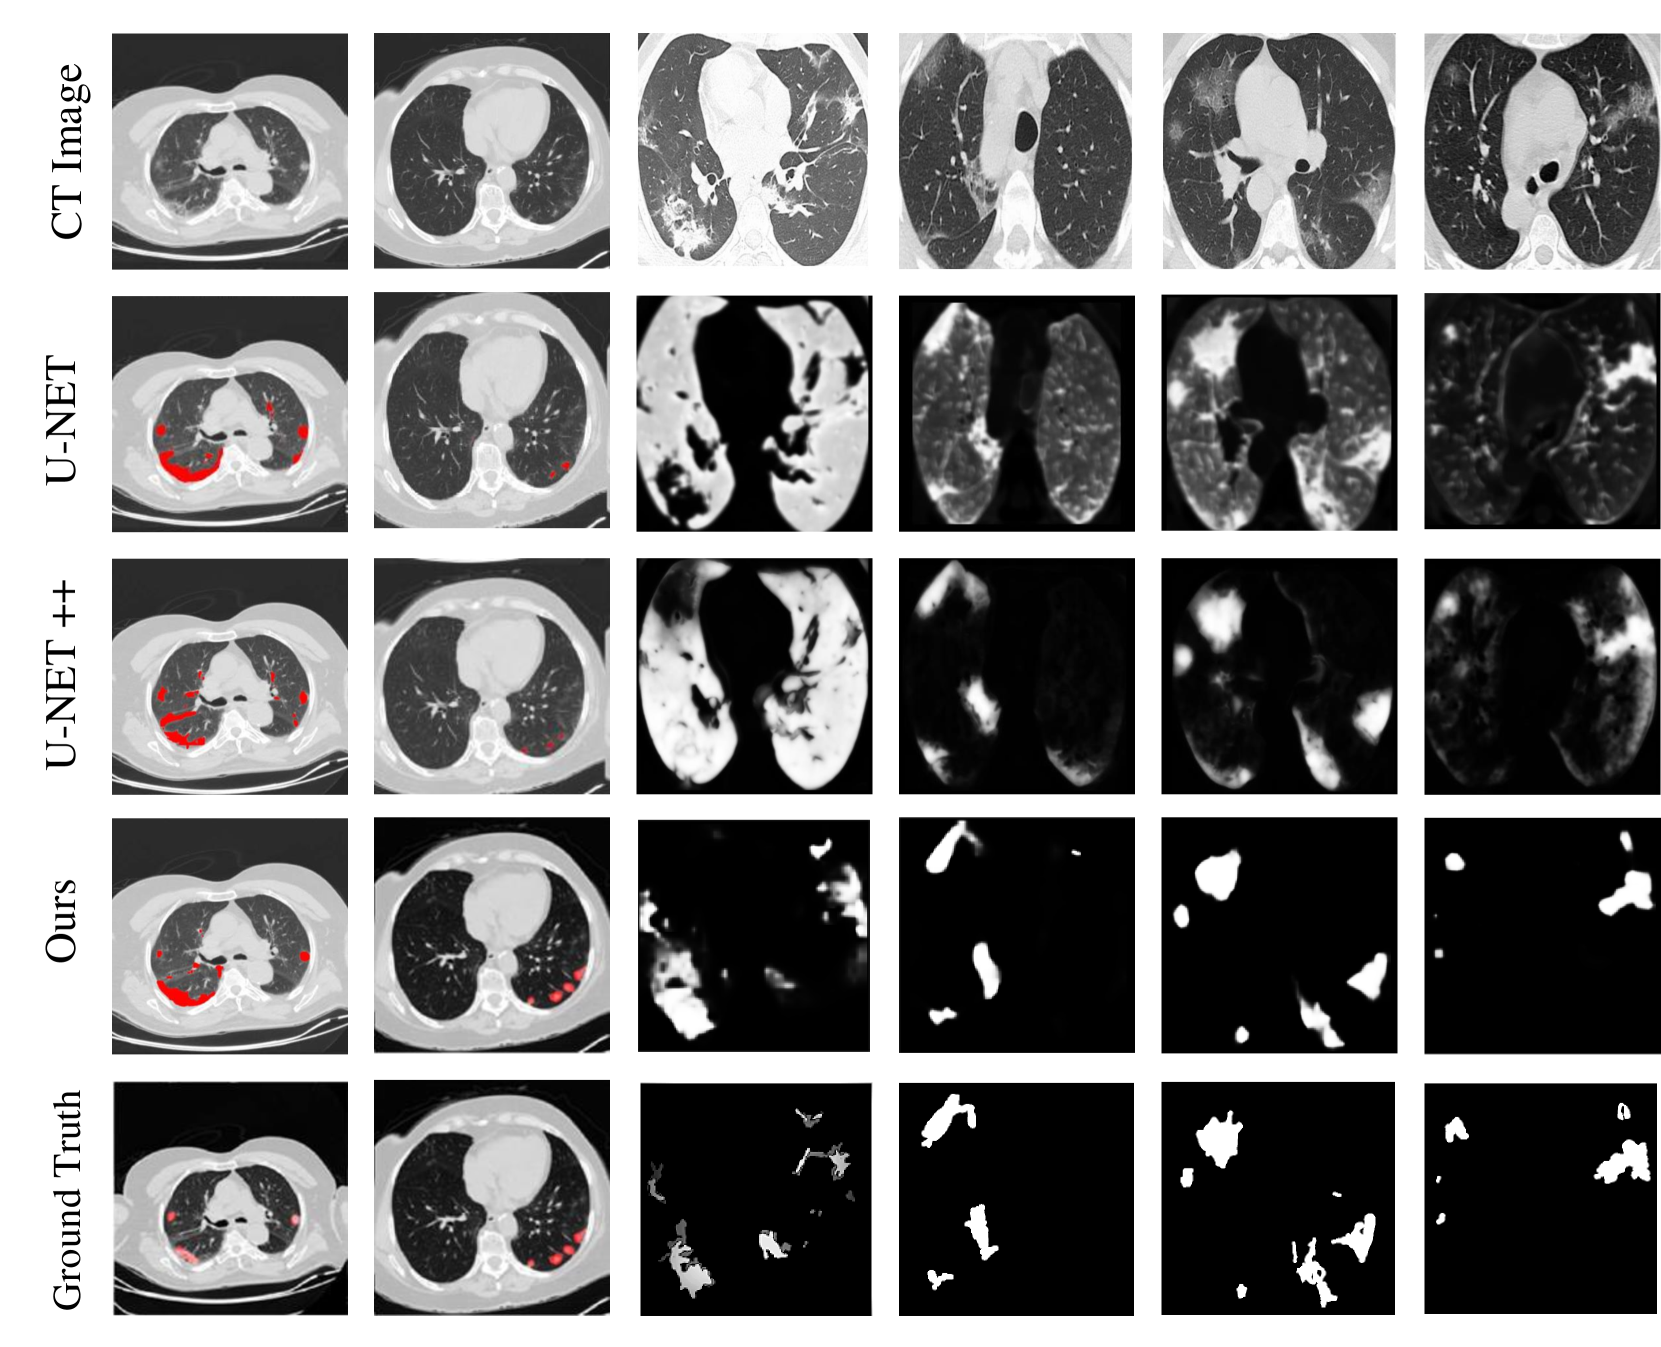

III-C Results of the pattern recognition with the benchmark algorithms

We performed comprehensive experiments using different kinds of deep learning models i.e.,(VGG16, AlexNet, Inception V3, ResNet 50-152 layers, MobileNet, DenseNet). We used deep learning models and different layers for comparing the performance models on the COVID-19 dataset, which is shown in Table IV. We evaluate the performance of the Capsule Network for the detection of COVID-19 lung CT image accuracy. Figure 8 shows the deep learning models; the Capsule Network achieves high sensitivity and less specificity, we achieved high detection performance through the Capsule Network. Figure 9 shows the Segcaps based Capsule Network achieved the best performance and provide the highest sensitivity and lowest specificity. These models were tested using three different test lists containing about 11,450 CT scan slices. The COVID-19 infection segmentation shown in Figure 10, indicates our method outperforms the baseline methods. The proposed techniques’ results are close to the ground truth. In contrast, U Net++s’ performance is near to our results.

Refer to caption

Figure 10: A visual comparison (segmentation) of our method with other studies. The first row (CT-Images) represents the original images taken from different datasets. The first two columns show the overlay segmentation result while the rest of the columns represent the masks.